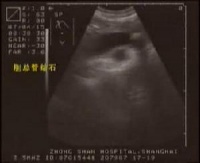

5.B超检查提示胆总管扩张、胆管内有结石。

3.B型超声波检查虽然价廉无创,对胆囊结石的准确率达98%,但因受十二指肠等空腔脏器的影响,对胆总管结石的准确率仅为50%左右,特别对十二指肠后段胆管难以显示。假阳性及假阴性率均较高。